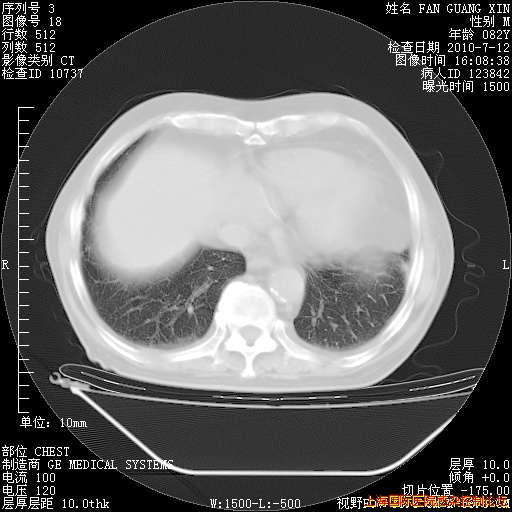

今天复查CT

今天CT

整整相隔30天的肺部CT好像有所好转啊。甲强龙减量第3天,需要观察体温。

海管,自昨日你和我通完话后,不知您岳父消化道症状有无缓解?体温怎样?阅读7.12日胸部ct,个人认为目前激素治疗是有效的,甲强龙减量是适宜的。因在抗痨治疗,需密切观察肝功、肾功能和血常规。不过,老年、长期住院和大量使用激素,很担心菌群失调发生